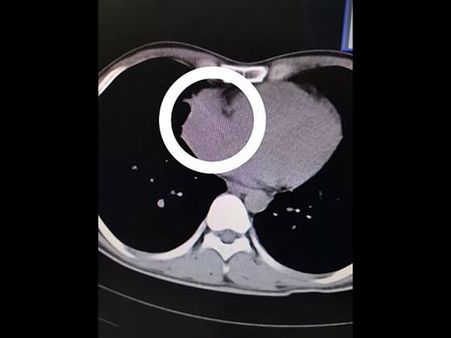

Doctors claim that the toothpick which was six centimetres long was found in Mr Zhou's right atrium. The toothpick had been drawn into the man's air passage and it had apparently pierced through the wall of the man's right lung before it stuck into his heart.